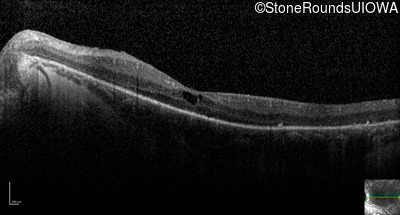

Optical Coherence Tomography - Left - 20/50

Exemplar / OCT Stack